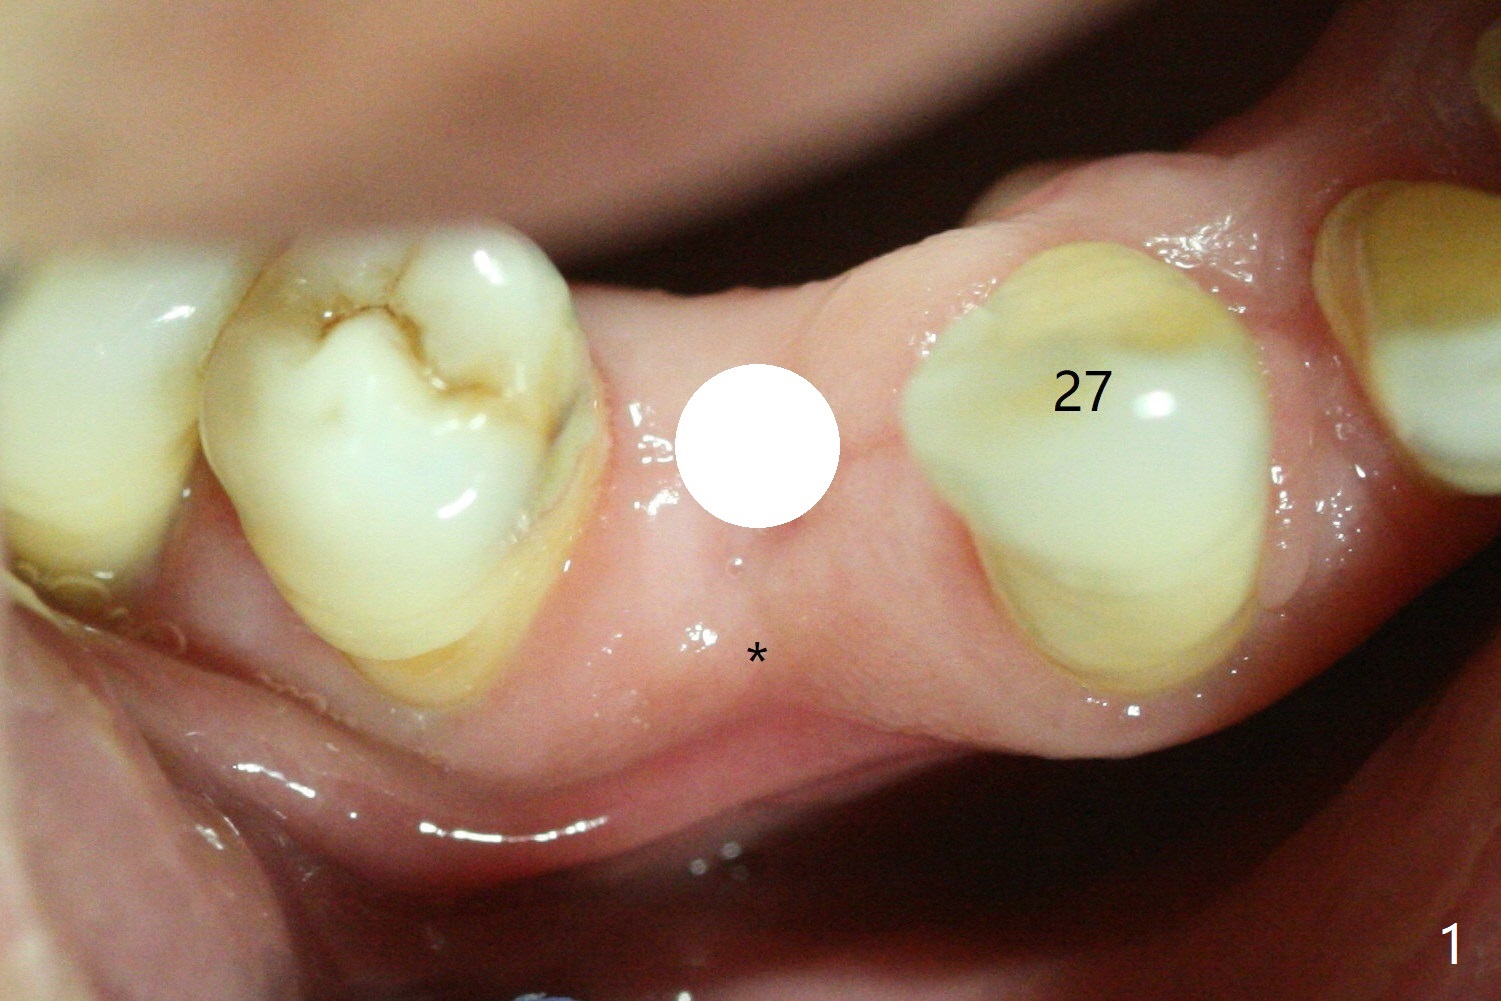

Ridge Split through Guide

Surgery begins with tissue punch or pointed drill

(Fig.1 white circle) through surgical guide at #28 with the concave buccal plate